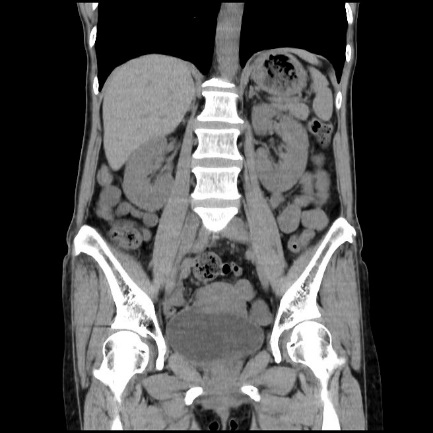

【CT(computed tomography)】

管球(ドーナツ状の部分にあるX線を出す機械)がX線を出しながら体の周りを回転し、人体を透過したX線をコンピューター処理して画像化します。短時間で広い範囲を撮影でき、様々な方向からの画像や3Dを作成します。